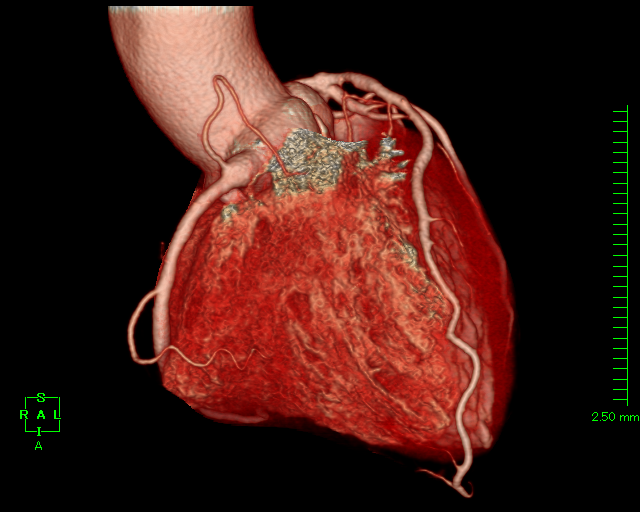

| 冠動脈CT検査 |

造影剤を使用し、心臓の血管(冠動脈)を撮影します。心臓は拍動しているので、心電図と同期させ高速に撮影します。 撮影した画像をワークステーションで処理することで、冠動脈の3D画像を作成したり、冠動脈の状態を確認できます。主に冠動脈の狭窄が疑われる患者様に行います。 |